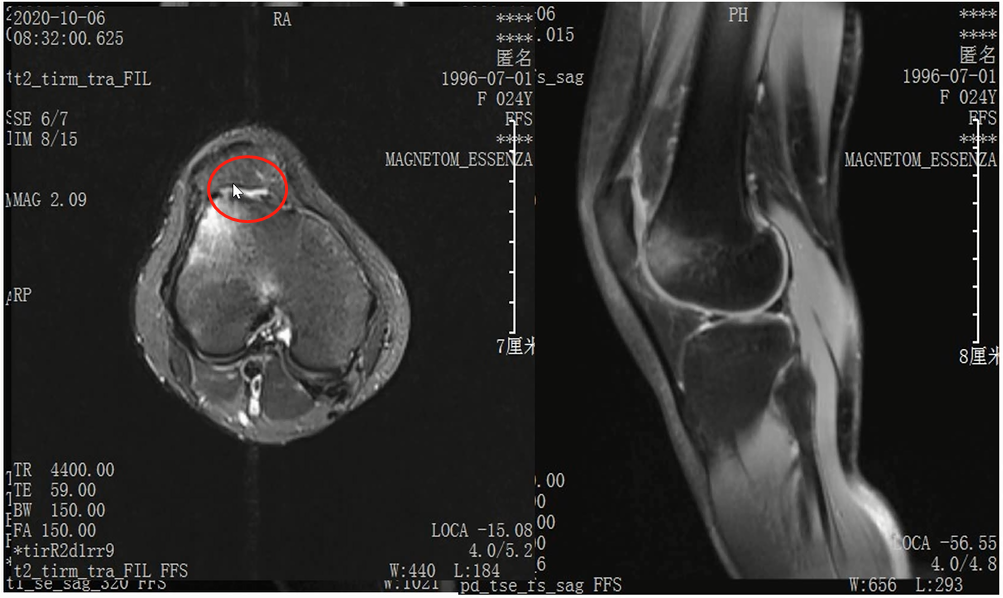

Lisfranc损伤在多发伤病人中常常容易漏诊,大约为 20-30%的漏诊率!